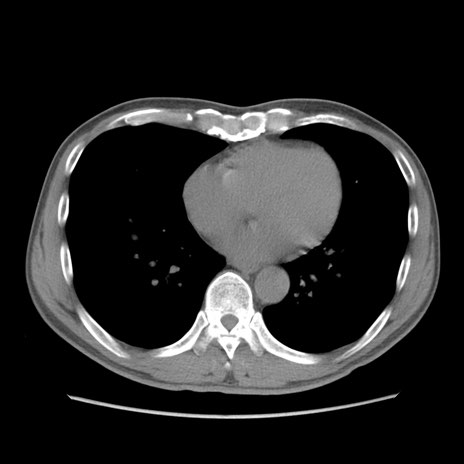

症例56 CT(横断像)

脂肪ウインドウ